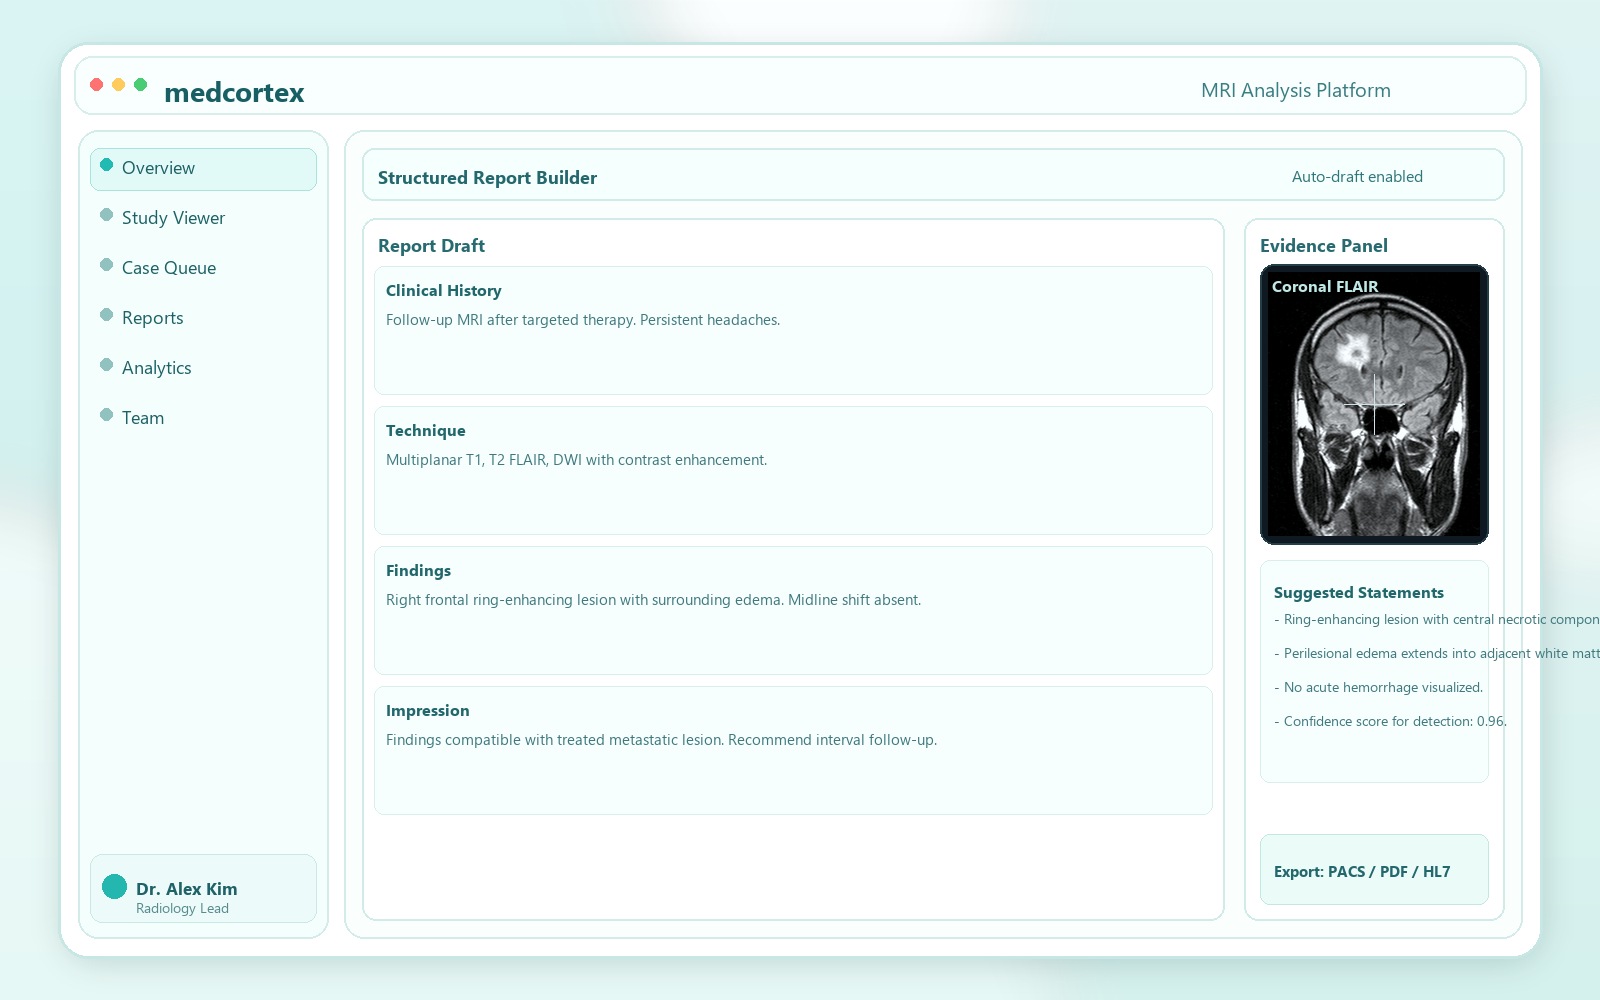

AI-powered MRI analysis for faster, clearer diagnosis support

Our in-house trained neural network highlights suspicious regions, quantifies change over time, and helps specialists prioritize urgent studies without disrupting existing workflows.